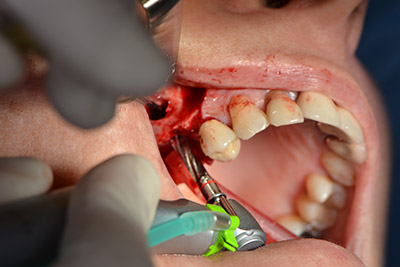

Il passaggio successivo consiste nel posizionamento dell'impianto, che nel nostro studio prevede una potenza pari a 32 Ncm (fig. 12).

Quindi, abbiamo optato per il rialzo del pavimento sinusale con impianto simultaneo. Implantmed è preimpostato sulla prima posizione per quanto riguarda la fenestrazione buccale della parete del seno mascellare.

La fenestrazione è impostata su 35.000 rpm, mentre la mucosa nasale viene preparata in direzione craniale (da fig. 13 a 14).